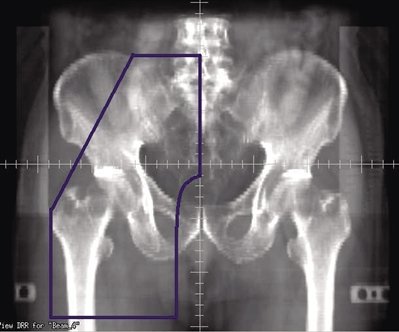

6 单侧盆腔野

肿瘤侵犯范围:一侧腹股沟/股三角/髂外淋巴结,任何一组或多组淋巴结受侵时,均采用同一照射野。

靶区定义:一侧腹股沟、股三角和髂外淋巴结(图6)。

上界:骶髂关节中部。如果髂总淋巴结受侵,放射野上界延伸至腰4~5椎体之间或受侵淋巴结上缘上2 cm。

下界:股骨小转子下5 cm。

外界:股骨大转子垂直向下或受侵淋巴结外缘外放2 cm。

内界:闭孔内缘,耻骨联合上2 cm,直至体中线。